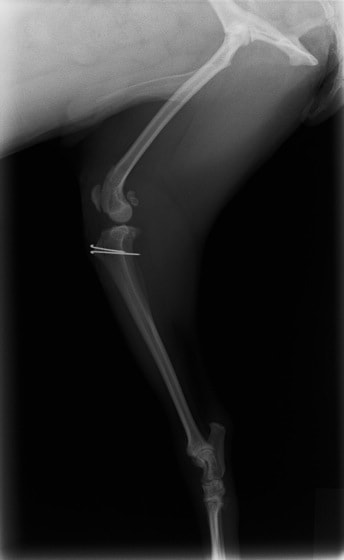

■ 症例20 ポメラニアン 8ヶ月 1.8kg

左右膝蓋骨脱臼 グレードⅢ

2ヶ月前から間欠的跛行が認められ、両膝の膝蓋骨脱臼整復術を行った。

手技は縫工筋及び内側広筋の解放、脛骨粗面の外側転位、滑車ブロック形造溝術、内外側関節包の縫縮を選択し実施した。

右側の膝蓋骨脱臼は上記手技で整復されたものの、左側はそれのみでは膝蓋骨が浮く様子が認められた。その為、PDS縫合糸にて膝蓋靱帯を1糸のみ縫合し、靱帯の縫縮を行った。

膝蓋骨脱臼は膝関節における膝蓋骨の内外側の脱臼と定義されるが、時として単純な内外の脱臼ではなく、膝蓋骨が大きく前方に浮き上がるように脱臼する場合がある。特にトイプードルやポメラニアンといった犬種に多く認められる。

内側脱臼に加えて前方への浮き上がりを矯正する為に、従来より脛骨粗面転移により膝蓋靭帯を外方と下方に引っ張り、固定する方法を選択する。膝蓋骨の前方への浮き上がりが軽度の場合は、従来法ではなく関節包の縫縮で対応していた。しかし、一部の症例で膝蓋骨の動きが悪くなり伸展機構が円滑に機能せずロボット様歩行になるケースがあった。

その為、膝蓋靭帯自体を縫縮する方法を採用した。この方法により、膝関節の伸展機構を妨げず膝蓋骨の軽度の浮きを矯正することが可能となった。

本症例の経過は良好である